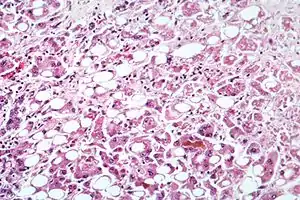

| Microscopy of liver showing fatty change, cell necrosis, Mallory bodies | |

Fatty change

Fatty change, or steatosis, is the accumulation of fatty acids in liver cells. These can be seen as fatty globules under the microscope. Alcoholism causes development of large fatty globules (macro-vesicular steatosis) throughout the liver and can begin to occur after a few days of heavy drinking.[9] Alcohol is metabolized by alcohol dehydrogenase (ADH) into acetaldehyde, then further metabolized by aldehyde dehydrogenase (ALDH) into acetic acid, which is finally oxidized into carbon dioxide (CO

2) and water (H

2O).[10] This process generates NADH, and increases the NADH/NAD+ ratio. A higher NADH concentration induces fatty acid synthesis while a decreased NAD level results in decreased fatty acid oxidation. Subsequently, the higher levels of fatty acids signal the liver cells to compound it to glycerol to form triglycerides. These triglycerides accumulate, resulting in fatty liver.

In people with alcoholic hepatitis, the serum aspartate aminotransferase (AST) to alanine aminotransferase (ALT) ratio is greater than 2:1. AST and ALT levels are almost always less than 500. The elevated AST to ALT ratio is due to deficiency of pyridoxal phosphate, which is required in the ALT enzyme synthetic pathway. Furthermore, alcohol metabolite–induced injury of hepatic mitochondria results in AST isoenzyme release. Other laboratory findings include red blood cell macrocytosis (mean corpuscular volume > 100) and elevations of serum gamma-glutamyl transferase (GGT), alkaline phosphatase, and bilirubin levels. Folate level is reduced in alcoholic patients due to decreased intestinal absorption, increased bone marrow requirement for folate in the presence of alcohol, and increased urinary loss. The magnitude of leukocytosis (white blood cell depletion) reflects severity of liver injury. Histologic features include Mallory bodies, giant mitochondria, hepatocyte necrosis, and neutrophil infiltration in the area around the veins. Mallory bodies, which are also present in other liver diseases, are condensations of cytokeratin components in the hepatocyte cytoplasm and do not contribute to liver injury. Up to 70% of patients with moderate to severe alcoholic hepatitis already have cirrhosis identifiable on biopsy examination at the time of diagnosis.[13]